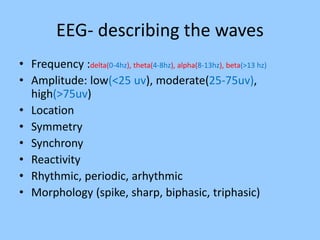

3. International standards for EEG electrode placement and recording parameters are reviewed. Characteristics of different EEG waves, amplitudes, and patterns are described.